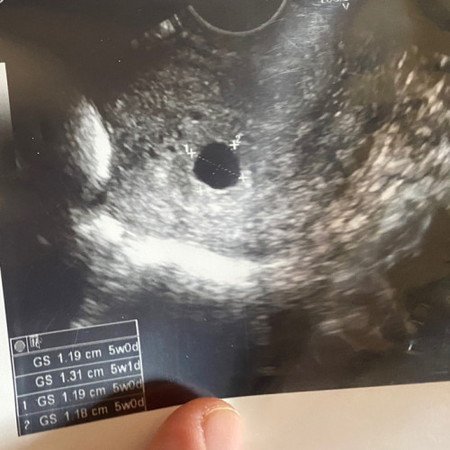

5วีคแล้วครับ ถุงใหญ่ขึ้นจาก4วีค แต่ยังไม่เจอน้อง มีสิทธิจะเจอน้องมั้ยคะแม่ๆ หมอนัดอีกที2อาทิตย์ 🏃🏃(แต่เลือดยังไม่หยุดตั้งแต่4วีค) คุณหมอไม่ได้ให้ยาหรือฉีดยาเพราะยังไม่เจอตัวน้อง